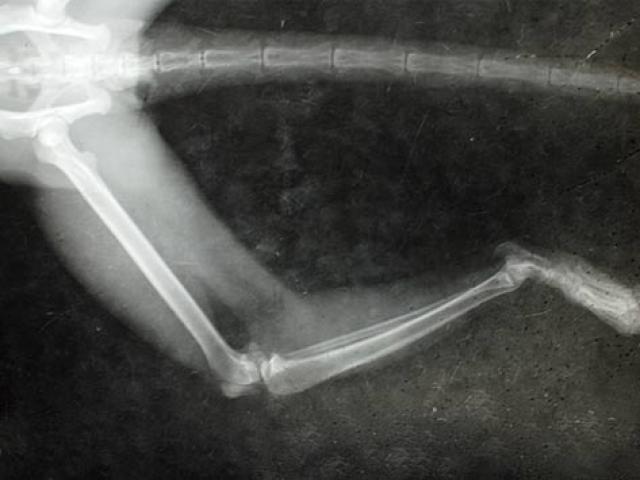

Fractured Bones In Reptiles Broken Bone In Reptile Petmd